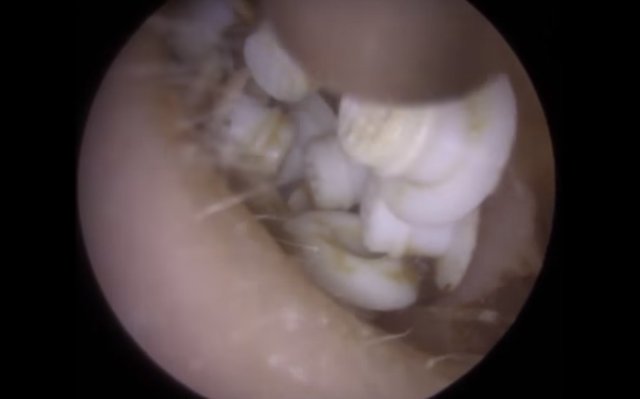

30 yıl boyunca geçmeyen bir baş ağrısı ile yaşayan bir kişi gittiği doktoru şoke etti. Yıllarca baş ağrısı çeken 59 yaşındaki adamın yaşadıkları kan dondurdu. Adamın kafasından öyle bir şey çıktı ki, doktorlar bile şaştı kaldı. İşte şoke eden olayın detayları...